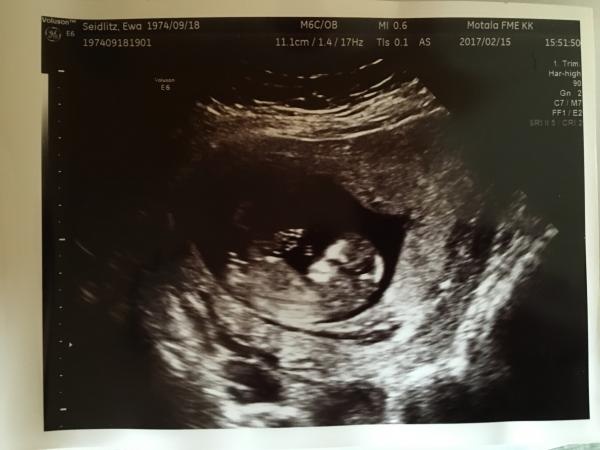

dunderida skrev 2017-02-22 19:28:45 följande:

Hej, gissa gärna på min :)

Tror på tjej dels på skallen.. då nubben är svår att se.. samt känsla :)